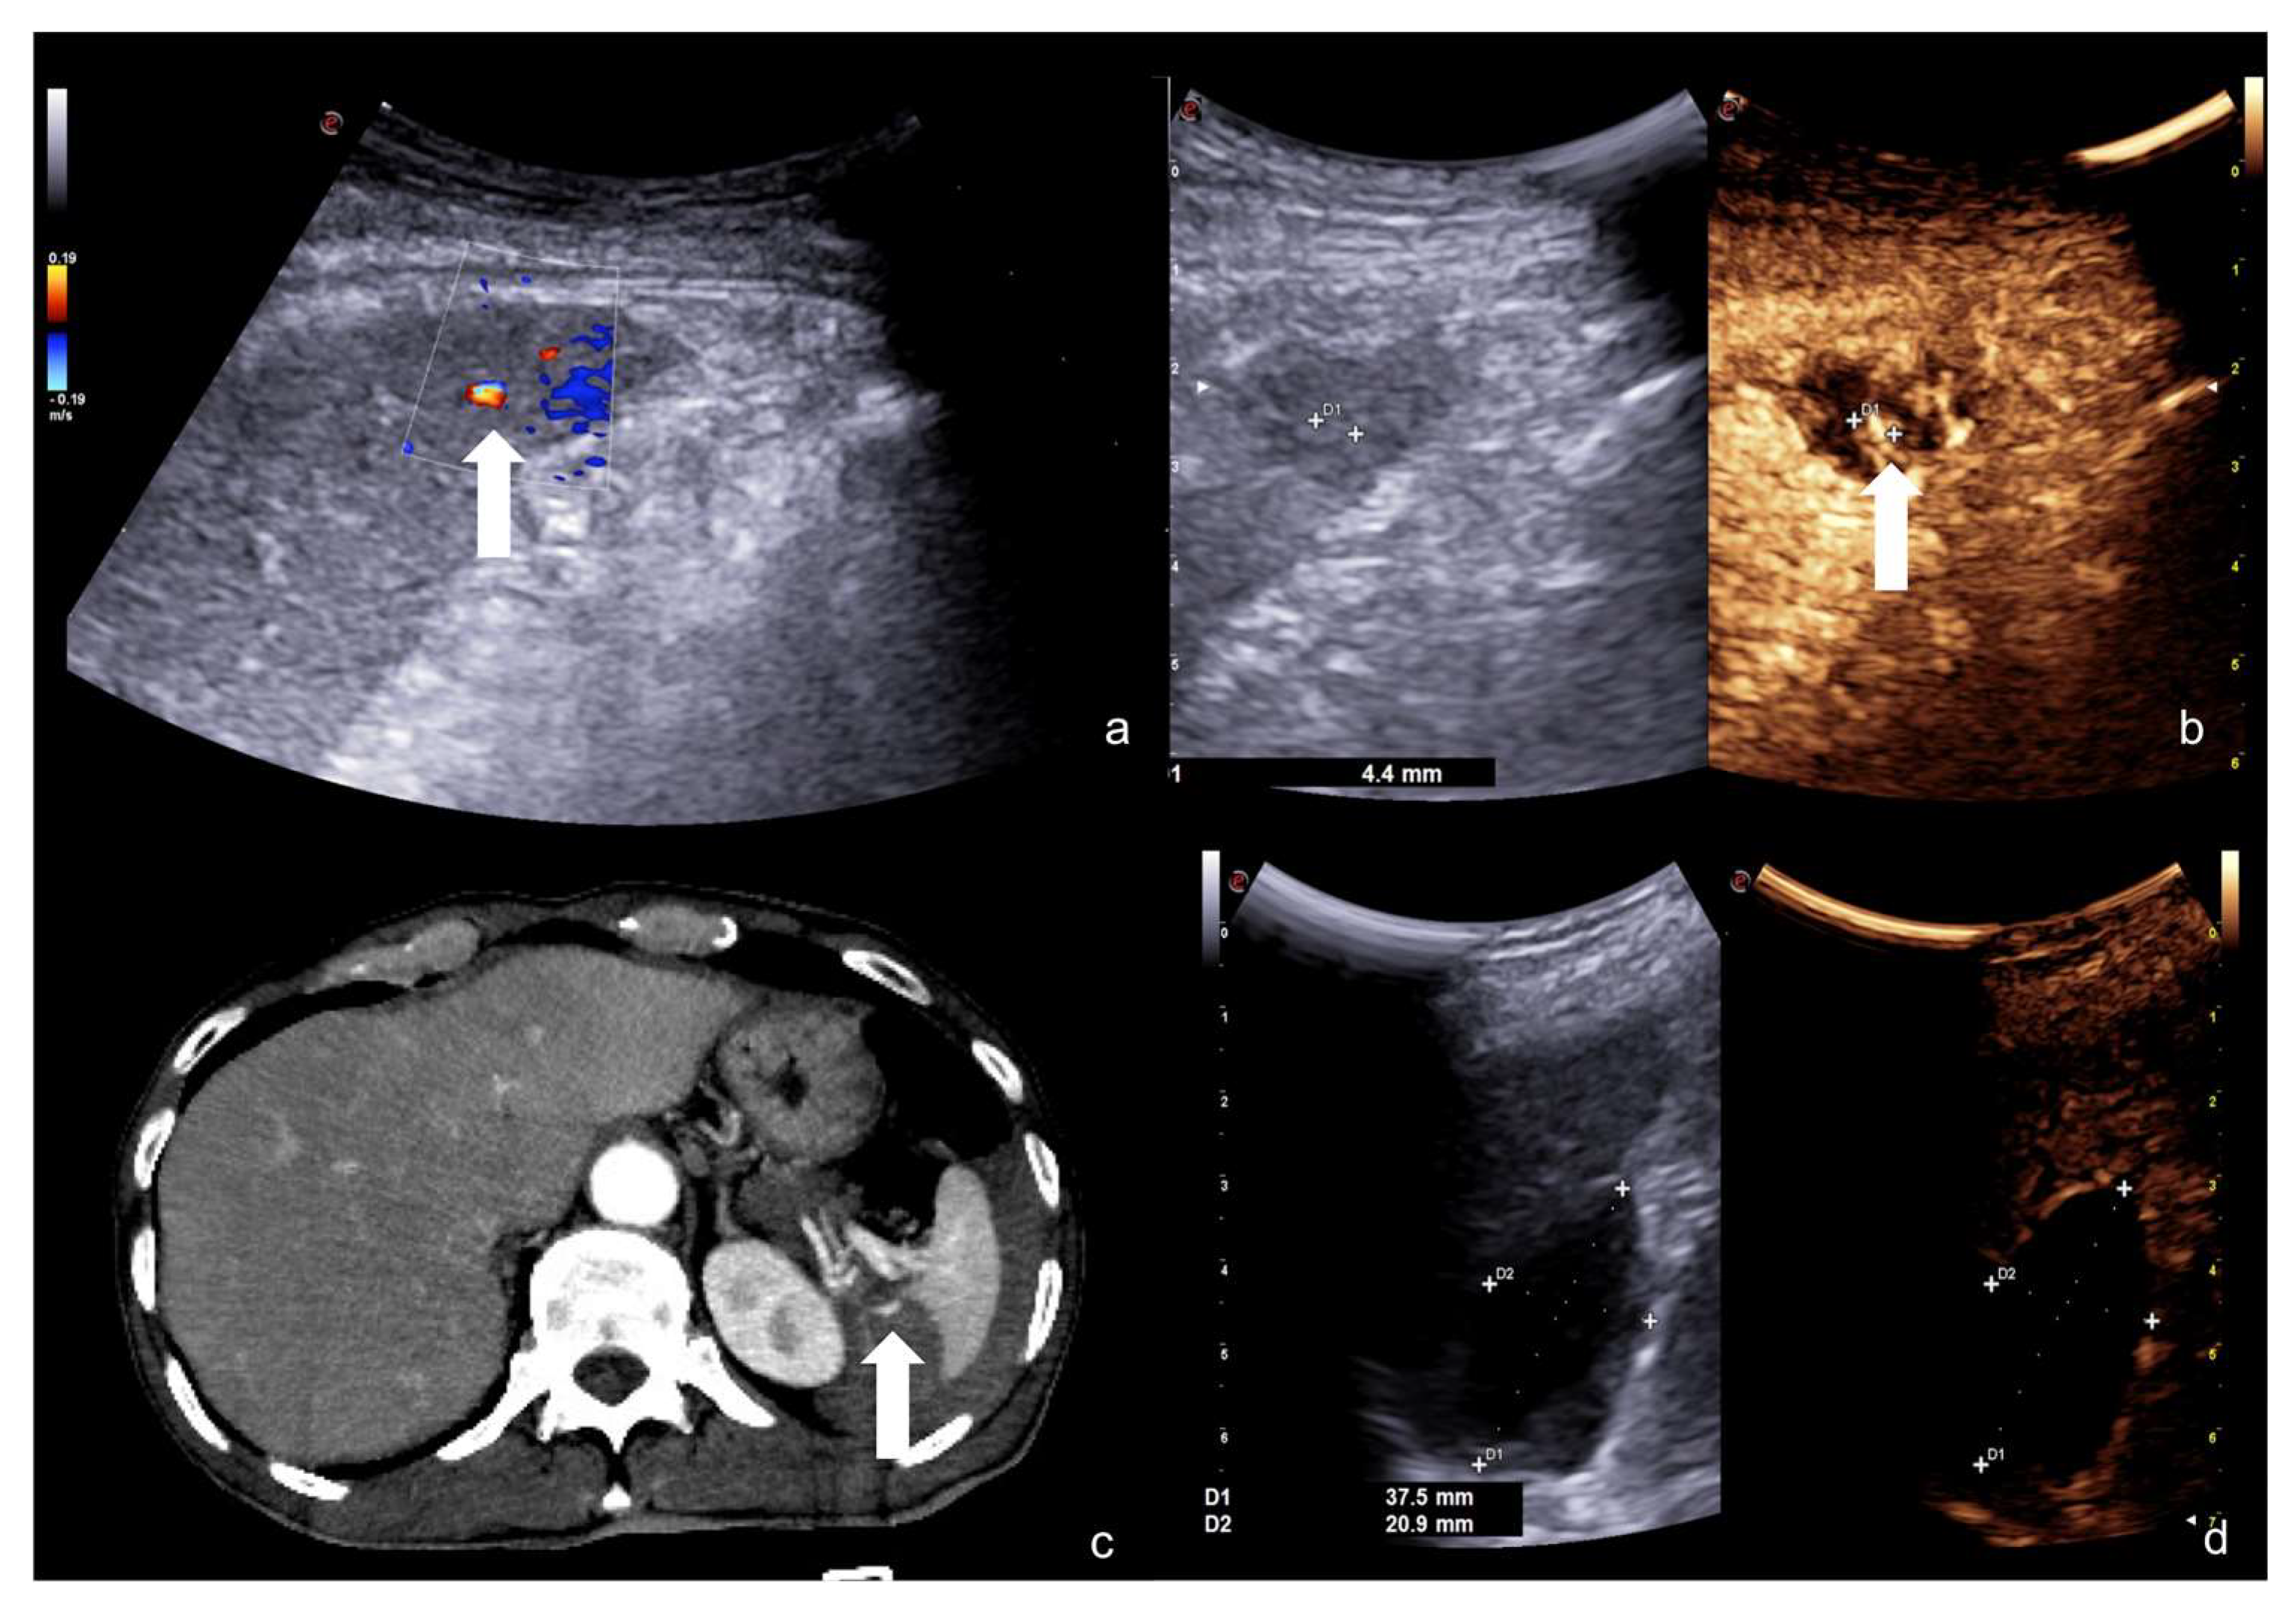

2.3.2. Vascular Injuries

- Active bleeding:

- Contained vascular injuries:

4. Case Series: Step-by-Step Practical Applications, Tips and Tricks during CEUS Follow-Up of Conservatively Managed Abdominal Trauma

4.1. Step 1

4.2. Step 2

4.3. Step 3

4.4. Step 4

4.5. Step 5